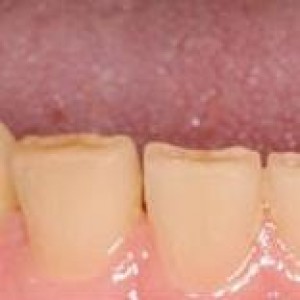

Obiettivi. Lo scopo di questo articolo è descrivere una serie di tecniche utili a migliorare l'estetica delle riabilitazioni implantari nel mascellare anteriore.Materiali e metodi. Si descrive...